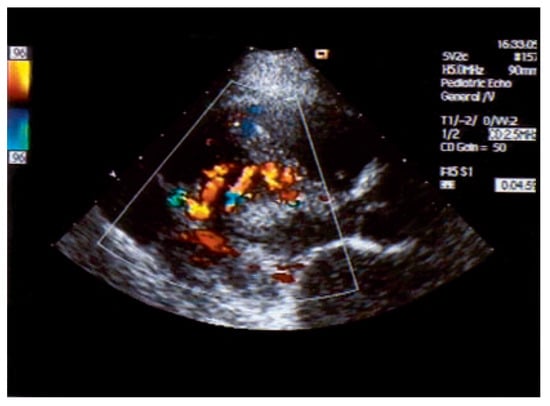

Asymptomatic Bland-White-Garland Syndrome in a 13-Year-Old Girl

by Jean-Pierre Pfammatter, Mladen Pavlovic and Stephan Windecker

An otherwise healthy 13-year-old girl was referred to the pediatric cardiology outpatient clinic for evaluation of a newly observed systolic murmur [...] Full article

Show Figures

Figure 1